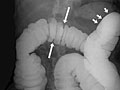

• In a double-contrast or air-contrast study, the colon is first filled with barium, and then the barium is drained out. This leaves only a thin layer of barium on the wall of the colon. The colon is then filled with air. This provides a detailed view of the inner surface of the colon. It makes it easier to see narrowed areas (strictures), diverticula, and swelling.

• Sacs in the colon wall (diverticulosis).